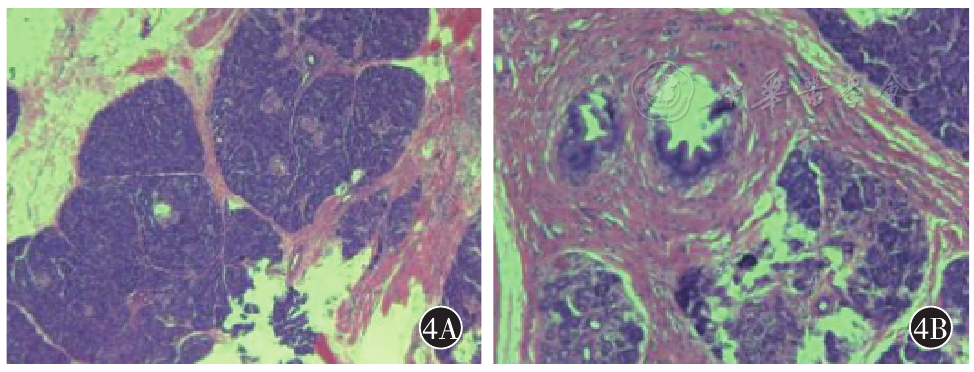

图4 术后病理(400x)